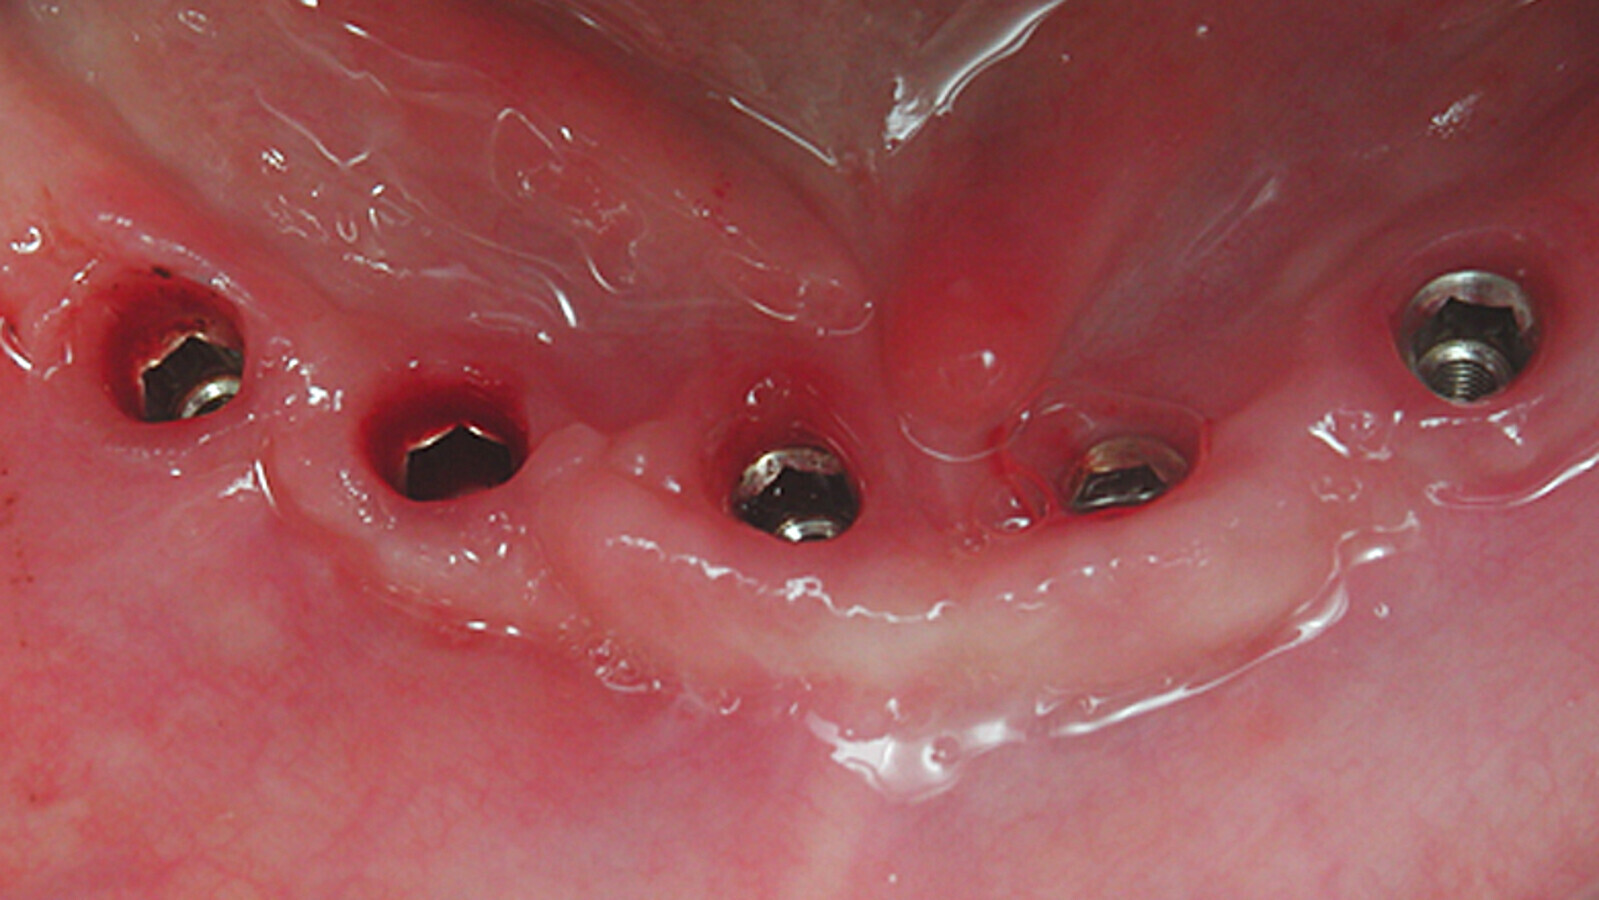

Fig. 5. Vista apical de la prótesis con su sistema de conexión-asentamiento.

Las prótesis se asientan en sus sistemas de conexión y los tornillos de fijación se torquean a la fuerza determinada por cada fabricante.

Idealmente, estos aparatos se debendesmontar una o dos veces al año para inspección visual, pero teniendo extremo cuidado con no correr los tornillos.